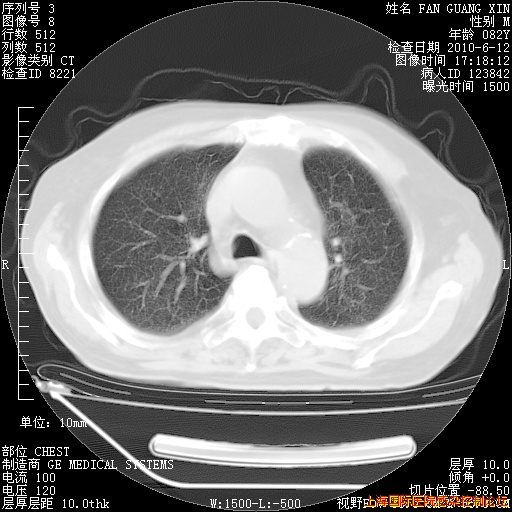

补发6月12日肺部CT肺窗

整整相隔30天的肺部CT好像有所好转啊。甲强龙减量第3天,需要观察体温。

海管,自昨日你和我通完话后,不知您岳父消化道症状有无缓解?体温怎样?阅读7.12日胸部ct,个人认为目前激素治疗是有效的,甲强龙减量是适宜的。因在抗痨治疗,需密切观察肝功、肾功能和血常规。不过,老年、长期住院和大量使用激素,很担心菌群失调发生